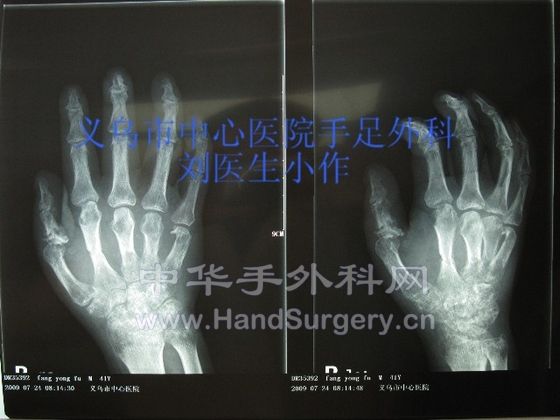

这是一例是高处电梯坠落所致严重压砸性加撕脱性断掌再植,术中处理较复杂,还望各位高手指点。目前术后有一定活动功能。

撕脱性断掌再植 (1).JPG

撕脱性断掌再植 (2).JPG

请问楼主骨折是用什么方法处理的 有没术前、后X片.....期待